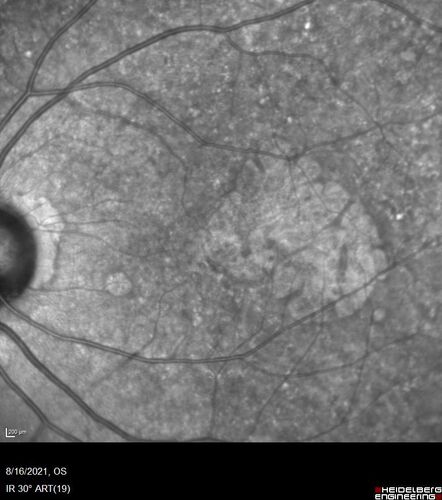

Geographic Atrophy with recent vision loss left eye

80 year old Recent vision loss in the left eye for about 6 weeks.

Hyperlipidemia, HTN, Angina, history of TIA’s

ASA daily

VA 20/25 OD, 20/63 OS (was 20/40 5/3/21 at patients first visit)

AC pseudophakic